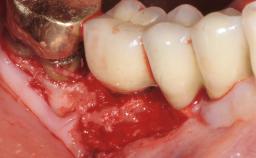

Treatment of Advanced Peri-Implantitis by Implant Removal Followed by Bone Reconstruction and New Implant Placement

Paolo Casentini and Matteo Chiapasco present a case in which the peri-implant defect was not suitable for a fully regenerative approach. It involves implant removal, use of a CAD/CAM customized titanium mesh in the grafting phase, and placement of new implants. A 62-year-old woman was referred for consultation regarding her implant-supported prosthesis replacing teeth 14 to 16. The patient’s main concern was pain and recurrent swelling in the right posterior maxilla. The patient also reported difficulty and discomfort when brushing the area. The patient reported she had been treated in another country, where she had received three implants in combination with sinus-floor augmentation for the replacement of the posterior maxillary teeth three years earlier. The patient indicated “endodontic complications” to be the reason for the extraction of the teeth.